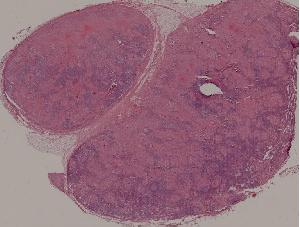

89.淋巴结结核